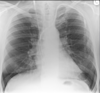

What is this ?